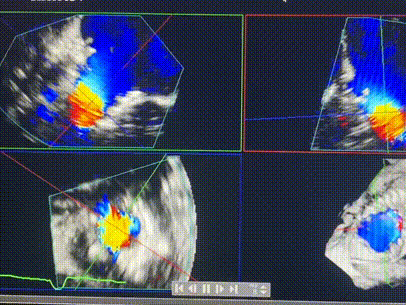

術(shù)前超聲提示重度三尖瓣反流

術(shù)中輸送器在超聲引導下調(diào)整位置